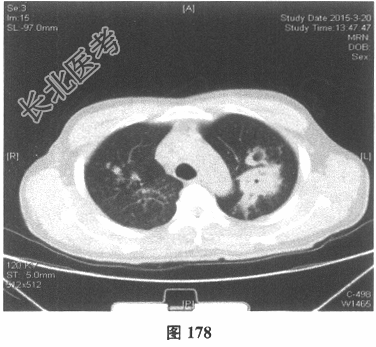

- [材料题] 患者男性,52岁,因间断发热伴咳嗽,咳少许黄痰,无咯血,伴胸闷憋气20余天就诊。体检:体温37.6~38.3℃。既往体健。查体:体温37.6℃,心率83次/分,呼吸20次/分,血压117/64mmHg。神志清,精神可,口唇无发绀;双肺呼吸音粗,可闻及广泛干、湿性啰音,以干啰音为主;心率83次/分,律齐,各瓣膜听诊区未闻及病理性杂音;腹软,无压痛及反跳痛,肠鸣音3次/分,双下肢无水肿。血常规检查:白细胞计数26.32×109/L,中性粒细胞0.846,血红蛋白117g/L,血小板计数1911×109/L;C反应蛋白119.05mg/L。尿常规检查:隐血2(+),蛋白1(+)。痰培养:曲霉菌属,请排除污染。生化全套检查:白蛋白19.6g/L,谷丙转氨酶24.2U/L,谷草转氨酶25.8U/L,γ-谷氨酰基转移酶91.4U/L;尿素氮13.00mmol/L(2.14~7.14mmol/L),肌酐166.8μmol/L(31~132μmol/L);血钾5.6mmol/L。肺部CT见图178~图185。